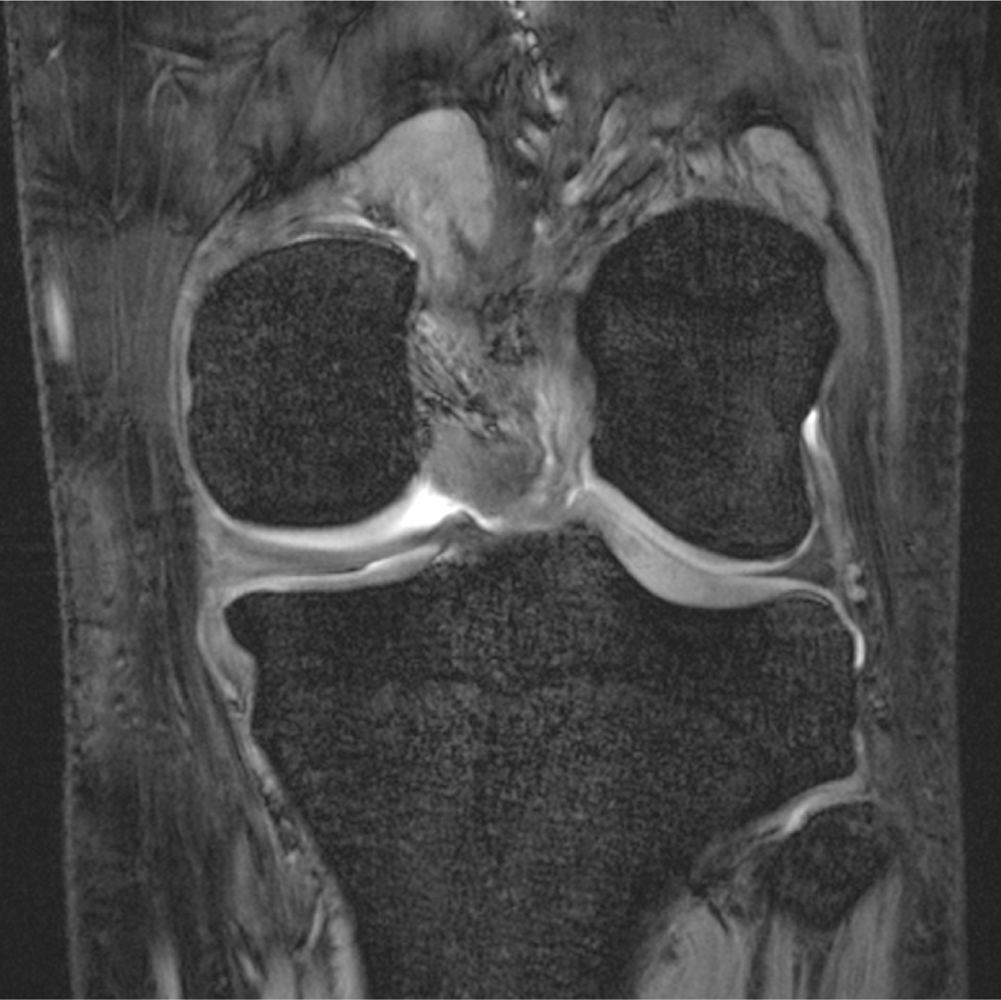

Advanced Morphological Imaging of Joints and Cartilage

2.1. High-Resolution Structural MRI

- Stahl, R.; Krug, R.; Kelley, D.A.; Zuo, J.; Ma, C.B.; Majumdar, S.; Link, T.M. Assessment of cartilage-dedicated sequences at ultra-high-field MRI: comparison of imaging performance and diagnostic confidence between 3.0 and 7.0 T with respect to osteoarthritis-induced changes at the knee joint. Skeletal. Radiol 2009, 38, 771–783. [Google Scholar]

- Kraff, O.; Theysohn, J.M.; Maderwald, S.; Saylor, C.; Ladd, S.C.; Ladd, M.E.; Barkhausen, J. MRI of the knee at 7.0 Tesla. Rofo 2007, 179, 1231–1235. [Google Scholar]